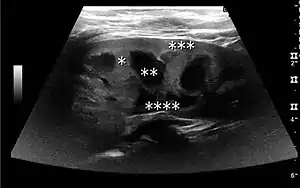

Figure 16. Hydronephrosis with dilated anechoic pelvis and calyces, along with cortical atrophy. The width of a calyx is measured on the US image in the longitudinal scan plane, and illustrated by ‘+’ and a dashed line.[1]

Figure 17. Same patient as in Figure 16 with measurement of the pelvis dilation in the transverse scan plane illustrated on the US image with ‘+’ and a dashed line.[1]